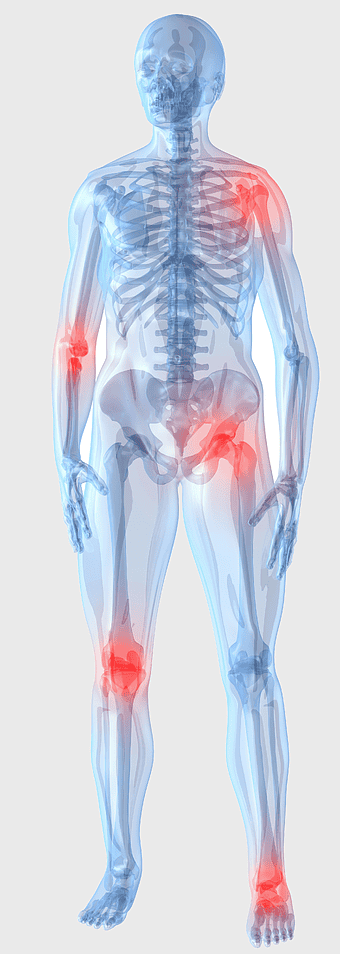

Knee pain management, arthritis joint therapy, human body musculoskeletal pain, low-level laser therapy for joints, osteoarthritis discomfort solutions, comprehensive joint health, systemic pain relief strategies -

arthritis pain symptoms, rheumatoid arthritis illustration, joint pain areas, human body anatomy, skeletal health issues, medical visualization, chronic joint discomfort -